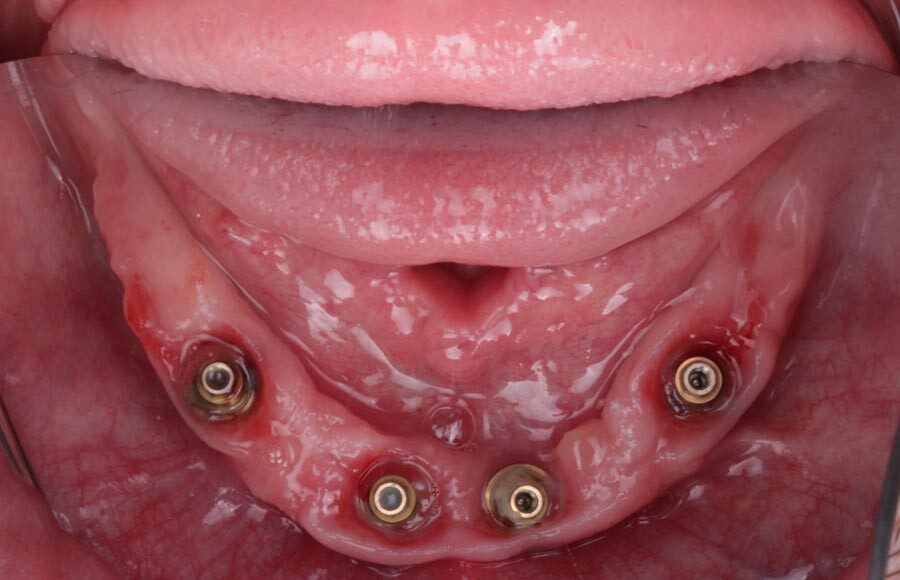

Smile GalleryImplant RestorationsImplant Dentures Post-op smiling 1 of 32 Pre-op close up smiling Pre-op lips retracted smiling Pre-op panoramic x-ray Implants in upper jaw (occlusal view) Implants in lower jaw (occlusal view) Panoramic x-ray of implants First set of try-ins – upper denture First set of try-ins – lower fixed provisional Delivered try-ins (lips retracted) Close adaptation to gums and appropriate emergence profile of lower fixed provisional Gum tissues have been molded by a convex provisional Delivered try-ins Second set of try-ins (lips retracted) Close adaptation to gums and appropriate emergence profile of second set of lower fixed provisional Delivered second try-ins Definitive restorations on casts (frontal view) Definitive restorations on cast (right side) Definitive restorations on cast (left side) Definitive upper overdenture (occlusal view) Definitive lower fixed titanium-acrylic hybrid restoration (occlusal view) Definitive lower fixed titanium-acrylic hybrid restoration (frontal view) Definitive lower fixed titanium-acrylic hybrid restoration (tissue side view) Healthy molded gum tissues on lower prior to delivery of lower fixed hybrid restoration Healthy gum tissues on upper prior to delivery of upper overdenture Definitive restorations (frontal, lips retracted) Definitive lower restoration (frontal) Definitive restorations (right side) Definitive restorations (left side) Definitive lower restoration (occlusal view) Definitive upper restoration (occlusal view) Post-op panoramic x-ray Post-op smiling